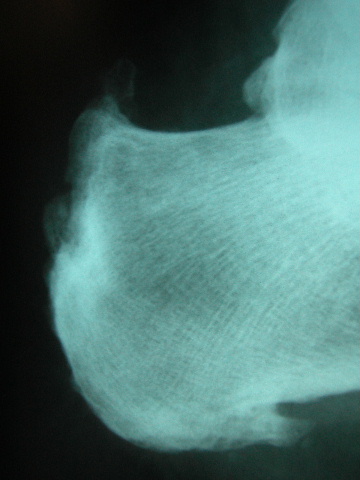

Densitometría en calcáneo